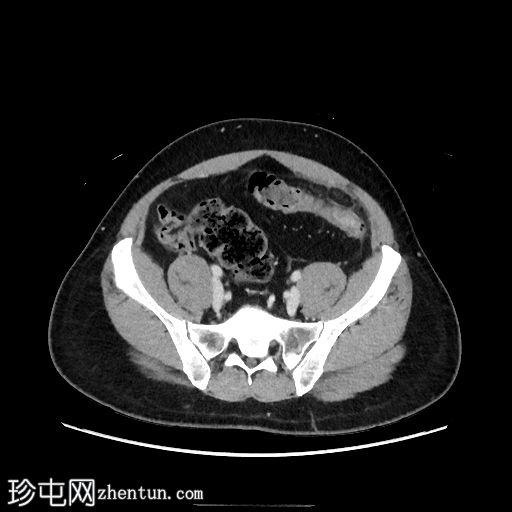

轴位

平扫

乙状结肠和远端降结肠可见轻度环周壁增厚

结肠周围可见卵圆形脂肪密度病变,周围环绕软组织密度环,并可见脂肪条索状改变,符合大网膜垂炎的典型表现

未见憩室炎证据